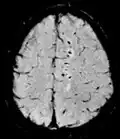

Susceptibility-weighted SWI Spoiled gradient recalled echo (GRE), fully flow compensated, long echo time, combines phase image with magnitude image[61] Detecting small amounts of hemorrhage (diffuse axonal injury pictured) or calcium.[61]

Inversion recovery Short tau inversion recovery STIR Fat suppression by setting an inversion time where the signal of fat is zero.[62] High signal in edema, such as in more severe stress fracture.[63] Shin splints pictured:

Fluid-attenuated inversion recovery FLAIR Fluid suppression by setting an inversion time that nulls fluids High signal in lacunar infarction, multiple sclerosis (MS) plaques, subarachnoid haemorrhage and meningitis (pictured).[64]

Double inversion recovery DIR Simultaneous suppression of cerebrospinal fluid and white matter by two inversion times.[65] High signal of multiple sclerosis plaques (pictured).[65]